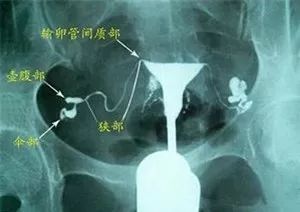

子宫输卵管造影术是目前被认为比较准确可靠的检查方法,根据使用的造影剂不同,可分为碘油造影和碘水造影。

主要操作方法是将双腔通水管插入子宫颈管向子宫腔内注入造影剂,通过X线透视和摄片或超声影像显影,根据造影剂在子宫、输卵管和盆腔内的显影情况分析输卵管的通畅程度、阻塞部位和宫腔形态。此检查客观直接,是不孕症有效的输卵管检查方法。